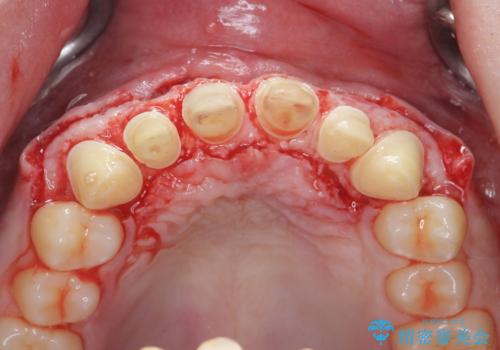

- 「前歯の見た目、歯ぐきの腫れを改善したい。」と希望され来院されました。

前歯には接着性の維持装置や、中途半端な形の連結クラウンが装着され、清掃性が悪く歯ぐきの腫れや、歯ぐきの形態の不揃いが認められました。

ただ、白いオールセラミッククラウンを製作・装着するのではなく、将来にわたり安定した状況を獲得するため、歯周外科を行い歯ぐきと周囲の歯槽骨の形態を整えていきます。

歯周外科を行ったことで、歯ぐきの形態や腫れが改善され、審美性だけでなく清掃性も大きく改善することができました。